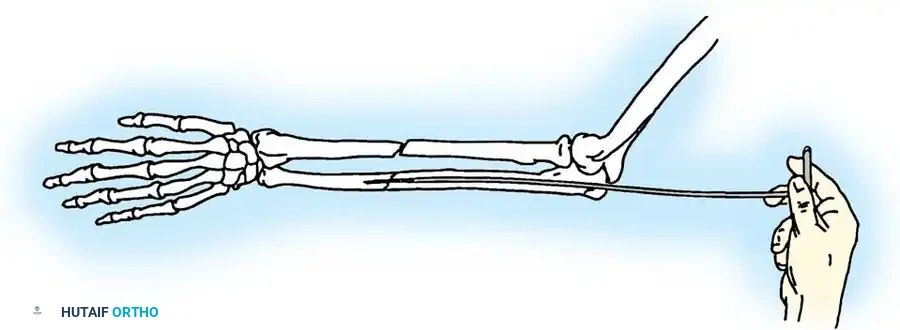

- Reduction and Compression: While an assistant grasps the proximal olecranon fragment with a large towel clip and exerts distal traction to anatomically reduce the fracture, twist the wire loop tightly.

Fig. 54-54 Internal fixation of olecranon with tension band wire loop. Wire passed through hole drilled in distal fragment and through triceps aponeurosis adjacent to bone. Figure-of-eight loop adds stability to fracture and prevents distraction and posterior bowing.